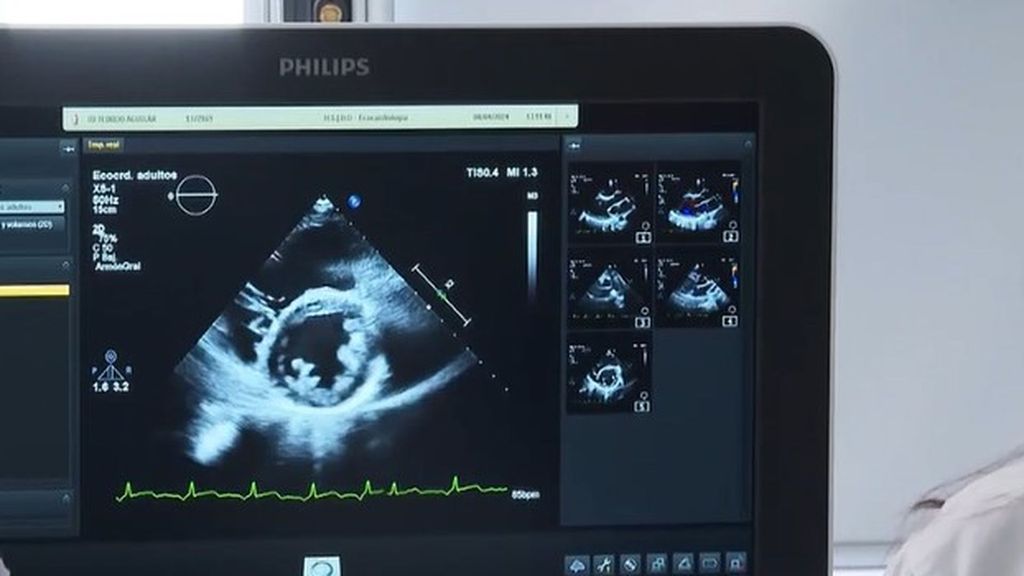

Para enseñarnos a reconocer los síntomas, Alfonso Núñez, reportero de 'Informativos Telecinco', ha entrevistado al doctor Roberto Barriales. El cardiólogo Roberto Barriales, del Complejo Hospitalario Universitario de A Coruña (CHUAC), explica que esta enfermedad consiste en un engrosamiento anormal del músculo cardíaco que, en muchos casos, puede pasar inadvertido.

Sin embargo, en algunos pacientes se manifiesta con síntomas como dolor torácico, síncopes o arritmias, llegando incluso a provocar la muerte súbita en un pequeño porcentaje de casos.